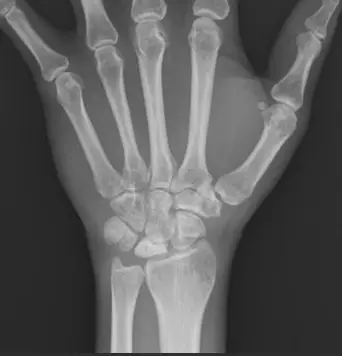

34歲男性長期在風濕免疫科就診,最近開始抱怨左手腕疼痛,醫師告知手腕的月狀骨(lunate bone )有異常。病人的手腕 X光片影像如圖所示,下列何者最可能造成月狀骨影像之異常?

- 解剖位置:X光片顯示為手腕的後前位(PA view)。在近端腕骨列(proximal carpal row)中央,與橈骨(radius)相接的骨頭即為 月狀骨(lunate bone)。

- 密度增加(Sclerosis):觀察影像中的月狀骨,其呈現的放射線密度明顯高於周圍的舟狀骨(scaphoid)或三角骨(triquetrum),看起來特別「白」。這是骨頭缺血性壞死早期的典型表現,稱為骨硬化(sclerosis)。

- 骨形狀:在此影像中,月狀骨尚未出現明顯的塌陷(collapse)或碎裂(fragmentation),這通常對應 Kienböck's disease 的 Lichtman Stage II(骨硬化期)。

- 其他骨骼:周圍骨骼未見明顯的關節間隙狹窄(joint space narrowing)或邊緣侵蝕(marginal erosions),這有助於排除典型的類風濕性關節炎或退化性關節炎。

- 影像:月狀骨明顯硬化(Sclerosis)。

- 影像證據確鑿:X 光片中最顯著的異常是月狀骨呈現瀰漫性高密度(變白),這是缺血性壞死(AVN)的標誌性影像(Sclerosis phase)。

- Stage II:骨硬化(Sclerosis),骨密度增加,無塌陷。(本題圖示階段)